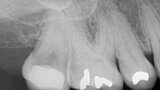

Clinical management of maxillary second molar root canal therapy in different anatomical situations